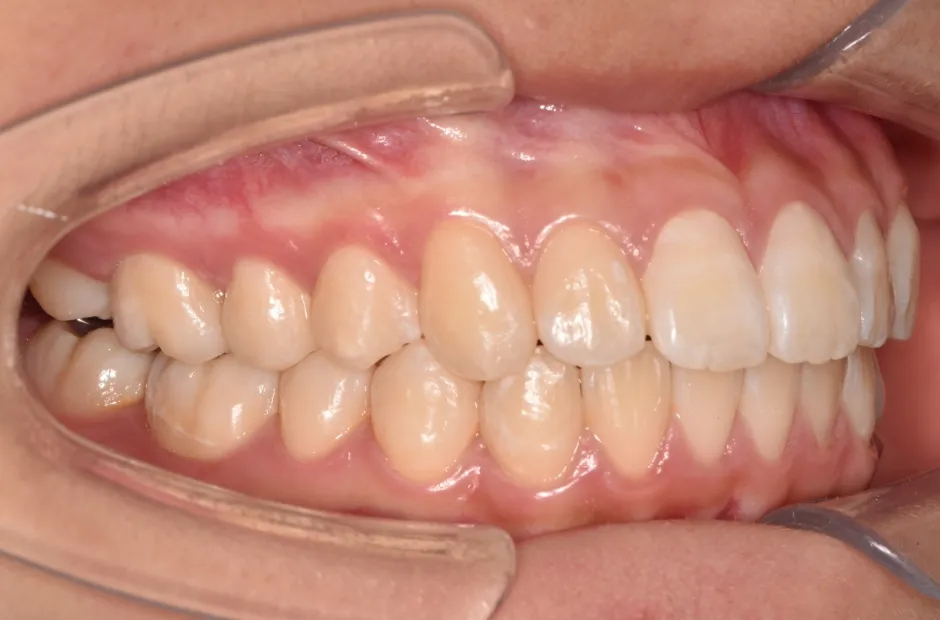

治療症例

ブラケット矯正

前歯部反対咬合

| 診断名・主訴 | 前歯部反対咬合 |

|---|---|

| 年齢・性別 | 14歳・男性 |

| 治療期間・回数 | 1年2か月 |

| 治療に用いた主な装置 | ブラケット矯正 |

| 抜歯部位 | なし |

| 治療費 | 60万円(税抜) |

| リスク・副作用 | 装置による違和感・疼痛・歯肉退縮・歯根吸収・虫歯のリスクなど |

治療後